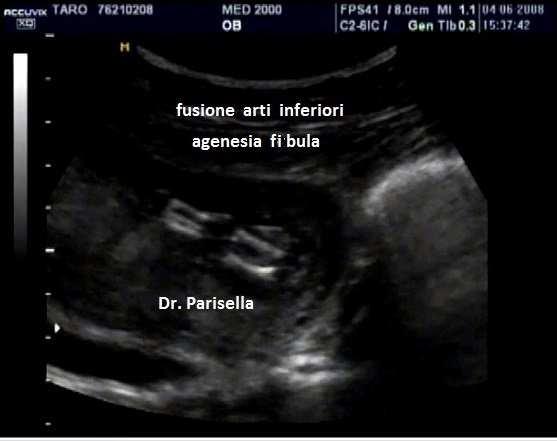

E' caratterizzata da deficit di vario grado di tutti e quattro gli arti (assenza di ulna e fibula con assenza o deficit severo degli arti come focomelia, oligodattilia, etc.), con ipoplasia o agenesia delle ossa del bacino (anche ipoplasia o agenesia del sacro), anomalie genitali consistenti in agenesia dell'utero e della vagina, micropene.

La diagnosi ecografica si basa principalmente sulle anomalie degli arti  e sull'agenesia del sacro.